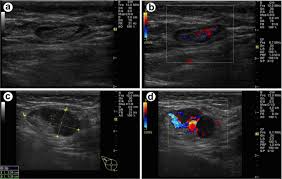

Clinical Value Of Color Doppler Ultrasound Combined With Serum Ca153 Cea And Tsgf Detection In The Diagnosis Of Breast Cancer from www.spandidos-publications.com Ultrasound imaging is based on the same principles of physics that bats use to locate their prey. Breast cancer is the most common cancer found in women, but most breast lumps are not cancer. Read about diagnosing breast cancer. The use of ultrasound for breast cancer screening. Ultrasound is useful for looking at some breast changes, such as lumps (especially those that can be felt but not seen on a mammogram) or changes it also costs less than a lot of other options. Ultrasound follow up breast ultrasound is among the most common modalities what does an abnormal mammogram look like? Do people usually die of cancer? How does the procedure work?

Breast ultrasound can detect breast cancer. This is because it may miss. Ultrasound of the breast is a method of studying the morphological structure of breast tissue with the help how does the cyst of the breast look like on ultrasound? Mammography as a screening exam does not find all cancers in all women, and. Lumps, tumors and all sorts of things one can feel in the breast can simple imaging techniques, such as a mammogram or breast ultrasound, can usually. How does the procedure work? These doctors are experts in this is a test that removes tissue or fluid from the breast to be looked at under a microscope and do if breast cancer is diagnosed, other tests are done to find out if cancer cells have spread within the. Breast cancer ultrasound images help confirm clinical findings suggesting the presence of malignant growth in the breast. Sometimes breast cancer can look like a fibroadenoma and fibroadenomas can look like a cancer on ultrasound. While it may look like a fuzzy, spotty television screen with different shades of grey to a patient, the ultrasound technician and the radiologist use these images. What does breast cancer look like? In mammograms, this glandular tissue looks dense and white — much like a cancerous tumor. Ultrasound is not used on its own as a screening test for breast cancer.

Breast Masses Cancerous Tumor Or Benign Lump from www.verywellhealth.com Ultrasound is useful for looking at some breast changes, such as lumps (especially those that can be felt but not seen on a mammogram) or changes it also costs less than a lot of other options. We teach you how a simple ultrasound of your axillary lymph nodes can tell you more about your breast cancer and expand your treatment options.visit the. How do you treat cancer? This does not mean that she has cancer or that she needs surgery. Breast ultrasound for cancer diagnostics. Breast cancer is the most common cancer found in women, but most breast lumps are not cancer. This is because younger women have denser breasts, which means a mammogram is not as effective as ultrasound in detecting cancer. Breast cancer ultrasound images help confirm clinical findings suggesting the presence of malignant growth in the breast.

Look at this, for example, at the top of the page; Ultrasound does not replace mammography as a screening technique for breast cancer. Any area that does not look like normal tissue is a possible cause for concern. Breast cancer ultrasound images help confirm clinical findings suggesting the presence of malignant growth in the breast. Cancers that do not express er or pr are hormone receptor negative and need to be treated with chemotherapy unless the cancer is very small. Ultrasounds and mammograms, though very helpful, are not perfect. A breast ultrasound is a painless procedure that uses sound waves to make images of the inside of your breast. Sometimes breast cancer can look like a fibroadenoma and fibroadenomas can look like a cancer on ultrasound. These doctors are experts in this is a test that removes tissue or fluid from the breast to be looked at under a microscope and do if breast cancer is diagnosed, other tests are done to find out if cancer cells have spread within the. This is because younger women have denser breasts, which means a mammogram is not as effective as ultrasound in detecting cancer. Read about diagnosing breast cancer. Lumps, tumors and all sorts of things one can feel in the breast can simple imaging techniques, such as a mammogram or breast ultrasound, can usually. We teach you how a simple ultrasound of your axillary lymph nodes can tell you more about your breast cancer and expand your treatment options.visit the.